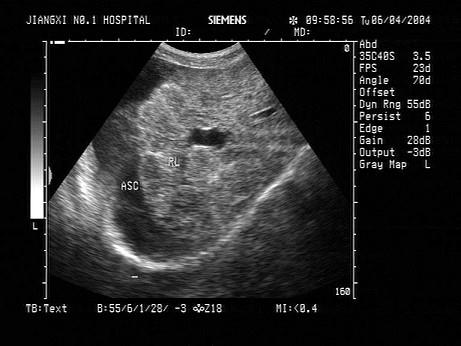

问题 男,70岁,上腹胀痛,腹膨隆。脾大,门静脉增宽。结合超声声像图,诊断为?(?)

选项 A.肝血管瘤 B.肝癌 C.血吸虫肝纤维化并腹水 D.肝脓肿 E.脂肪肝

答案 C